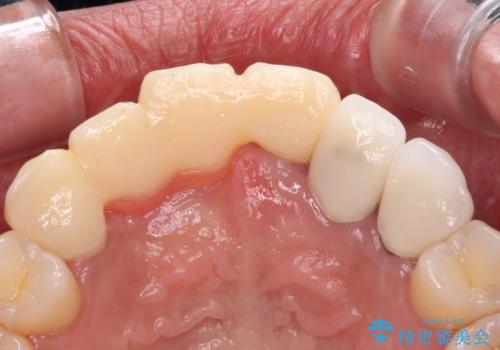

- 前歯を2本抜歯した後に装着した仮歯が長く見えるのが気になるとのことで来院された患者様です。

抜歯後には歯を支えていた骨が失われるため、歯肉が痩せてしまい、結果としてブリッジのダミーの歯を長くする必要があります。

前医では、歯肉の位置に相当する部分を、歯肉に近い色とすることで歯の長さが揃っているようにカムフラージュする治療が提案され、仮歯もそのようになっていました。

歯肉が痩せてしまっている状態を改善するため、口蓋から歯肉の結合組織を採取し、移植することで厚みを増大させることとし、その後オールセラミックブリッジにて補綴治療を行うこととしました。